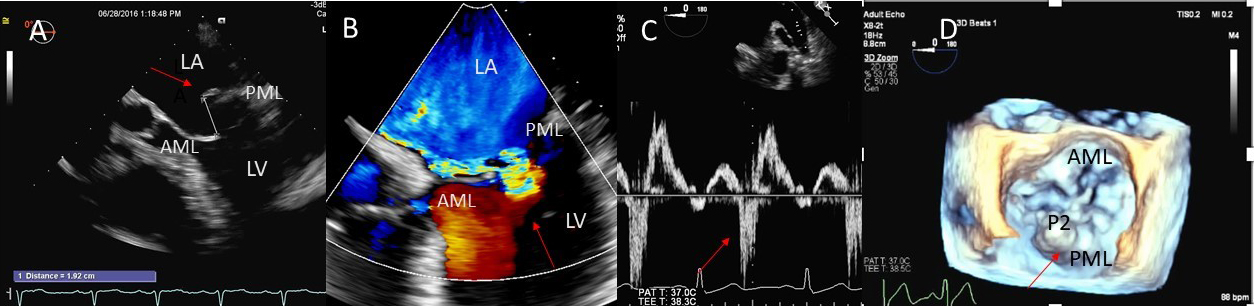

Besides prolapsing or flail scallops, MR jet may also originate between individual scallops. This occurs more commonly between the posterior leaflet through cleft like indentations that sometimes extend to the mitral annulus. This origin of MR can be very difficult to diagnose on 2D TTE or TEE (Fig. 2A–C). 3D color Doppler further assists in confirming jet origin at the site of suspected leaflet pathology/ies including presence of mitral valve cleft like indentation/s. Presence of calcification on the annulus and leaflets and in the subvalvular apparatus further assists surgeon in planning repair [21]. Visualization of the valve from the LV perspective adds further information on leaflet morphology, coaptation and regurgitant site/s particularly if jet originates from mitral valve clefts. Optimal visualization of the MR jets using real-time 3D TEE leads direct guidance for catheter movement and positioning of the implanted device(s) capturing the opposing sides of anterior and posterior mitral leaflet scallops during catheter based MV interventional procedures [22].

Fig. 2.Mitral leaflet Cleft. (A) TTE short axis at the mitral valve level showing posterior mitral cleft. (B, C) Isolated cleft within the P2 segment of the posterior leaflet (associated with mitral regurgitation) on 3D TEE and TTE short axis views. AML, anterior mitral leaflet; PML, posterior mitral leaflet.